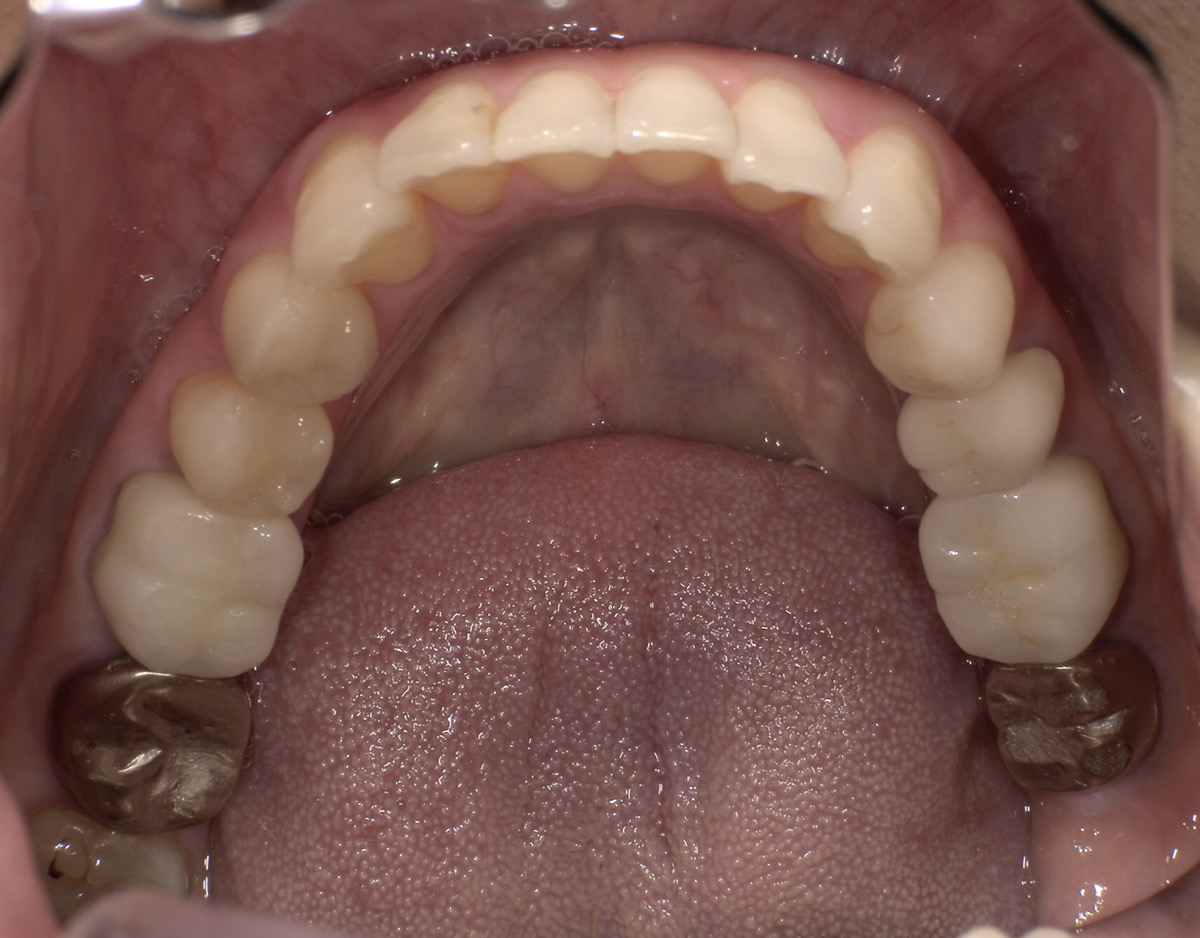

CASE 03

Before

After

施術内容左右下顎の第一・第二大臼歯の銀歯(被せ物)をジルコニアクラウンに交換。右下第二小臼歯の銀歯(詰め物)をジルコニアインレーに交換。

治療期間3か月

リスク・副作用ジルコニアは非常に強度が高いですが、強い衝撃や極端に強い噛み合わせ、歯ぎしり・食いしばりなどがある場合、まれに割れたり欠けたりする可能性があります。

費用 454,400円

※表示金額は全て税込みです。